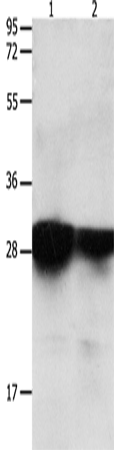

分类: 科研抗体货号: P11041别名: LPH, MSH, NPP, POC, ACTH, CLIP应用: WB,IHC反应种属: Human, Mouse